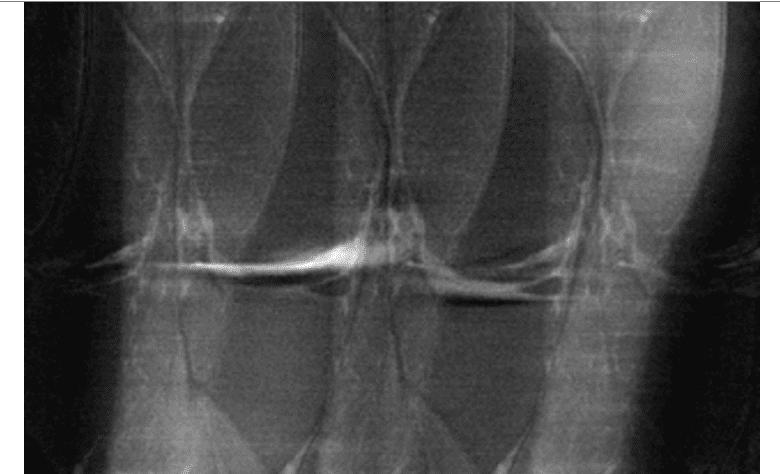

لا شك أن هذا المشروع يقدِّم منهجية مهمة لدمج الذكاء الاصطناعي في الطب؛ فغالباً ما يستخدم الذكاء الاصطناعي لتحليل ما الذي تحتويه الصور في الحياة اليومية، وقد تكون هذه الصور مثلاً لطبق باستا أو هوت دوغ رفعها أحد المستخدمين على حسابه في وقع يلب (Yelp)، أما في قطاع الطب، فقد بحثت العديد من الدراسات الحديثة إمكانية استخدام الذكاء الاصطناعي في اكتشاف مرض السل في فحوصات الرئة بالأشعة السينية أو اكتشاف علل الرُّكب في فحوصات التصوير بالرنين المغناطيسي. وفي عمل تعاوني بين شركة ديب مايند (التابعة لألفابيت، الشركة الأم لغوغل) ومستشفى مورفيلدز آي (Moorfields Eye) في إنكلترا، سيعمل الذكاء الاصطناعي على تحليل فحوصات ثلاثية الأبعاد للجزء الخلفي من عيون المرضى، بل من الممكن أن يقترح العلاج أيضاً.

وبطبيعة الحال تبدو فكرة “إنشاء صورة فحص بناء على بيانات خام أقل من المعتاد” فكرة خطرة، وتبرز أسئلة قلقة مثل: ماذا لو حوَّل الذكاء الاصطناعي تلك البيانات بطريقة تُنتج صورة جيدة لكنها تفوِّت شيئاً شديد الأهمية؟ تمزقاً ضئيلاً مثلاً في إحدى العضلات أو ورماً ضئيل الحجم؟ يدرك العلماء والباحثون في هذا المشروع هذه المخاوف؛ حيث يقول سوديكسون إنها تمثل أكبر حجر عثرة أمامهم حتى الآن، ويصرِّح “لا بد لنا أن نتأكد من إنتاج صور فحص تطابق الواقع والحقيقة”، ويضيف: “إن في جعبتنا الكثير من الطرق لاختبار ذلك”.